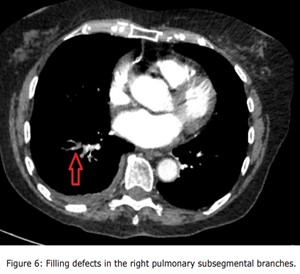

Given the persistent patient's symptoms despite completing the course of oral antibiotics, and raising D-dimer, a CTPA was performed to rule out PE which demonstrated multiple filling defects in the right lower pulmonary artery and its segmental with subsegmental branches, and patchy consolidations in the right lower lobe with mild right pleural effusion suggestive of infective/inflammatory aetiology ( Figure 3, Figure 4, Figure 5, Figure 6 and Figure 7).

Figure 6: Filling defects in the right pulmonary subsegmental branches